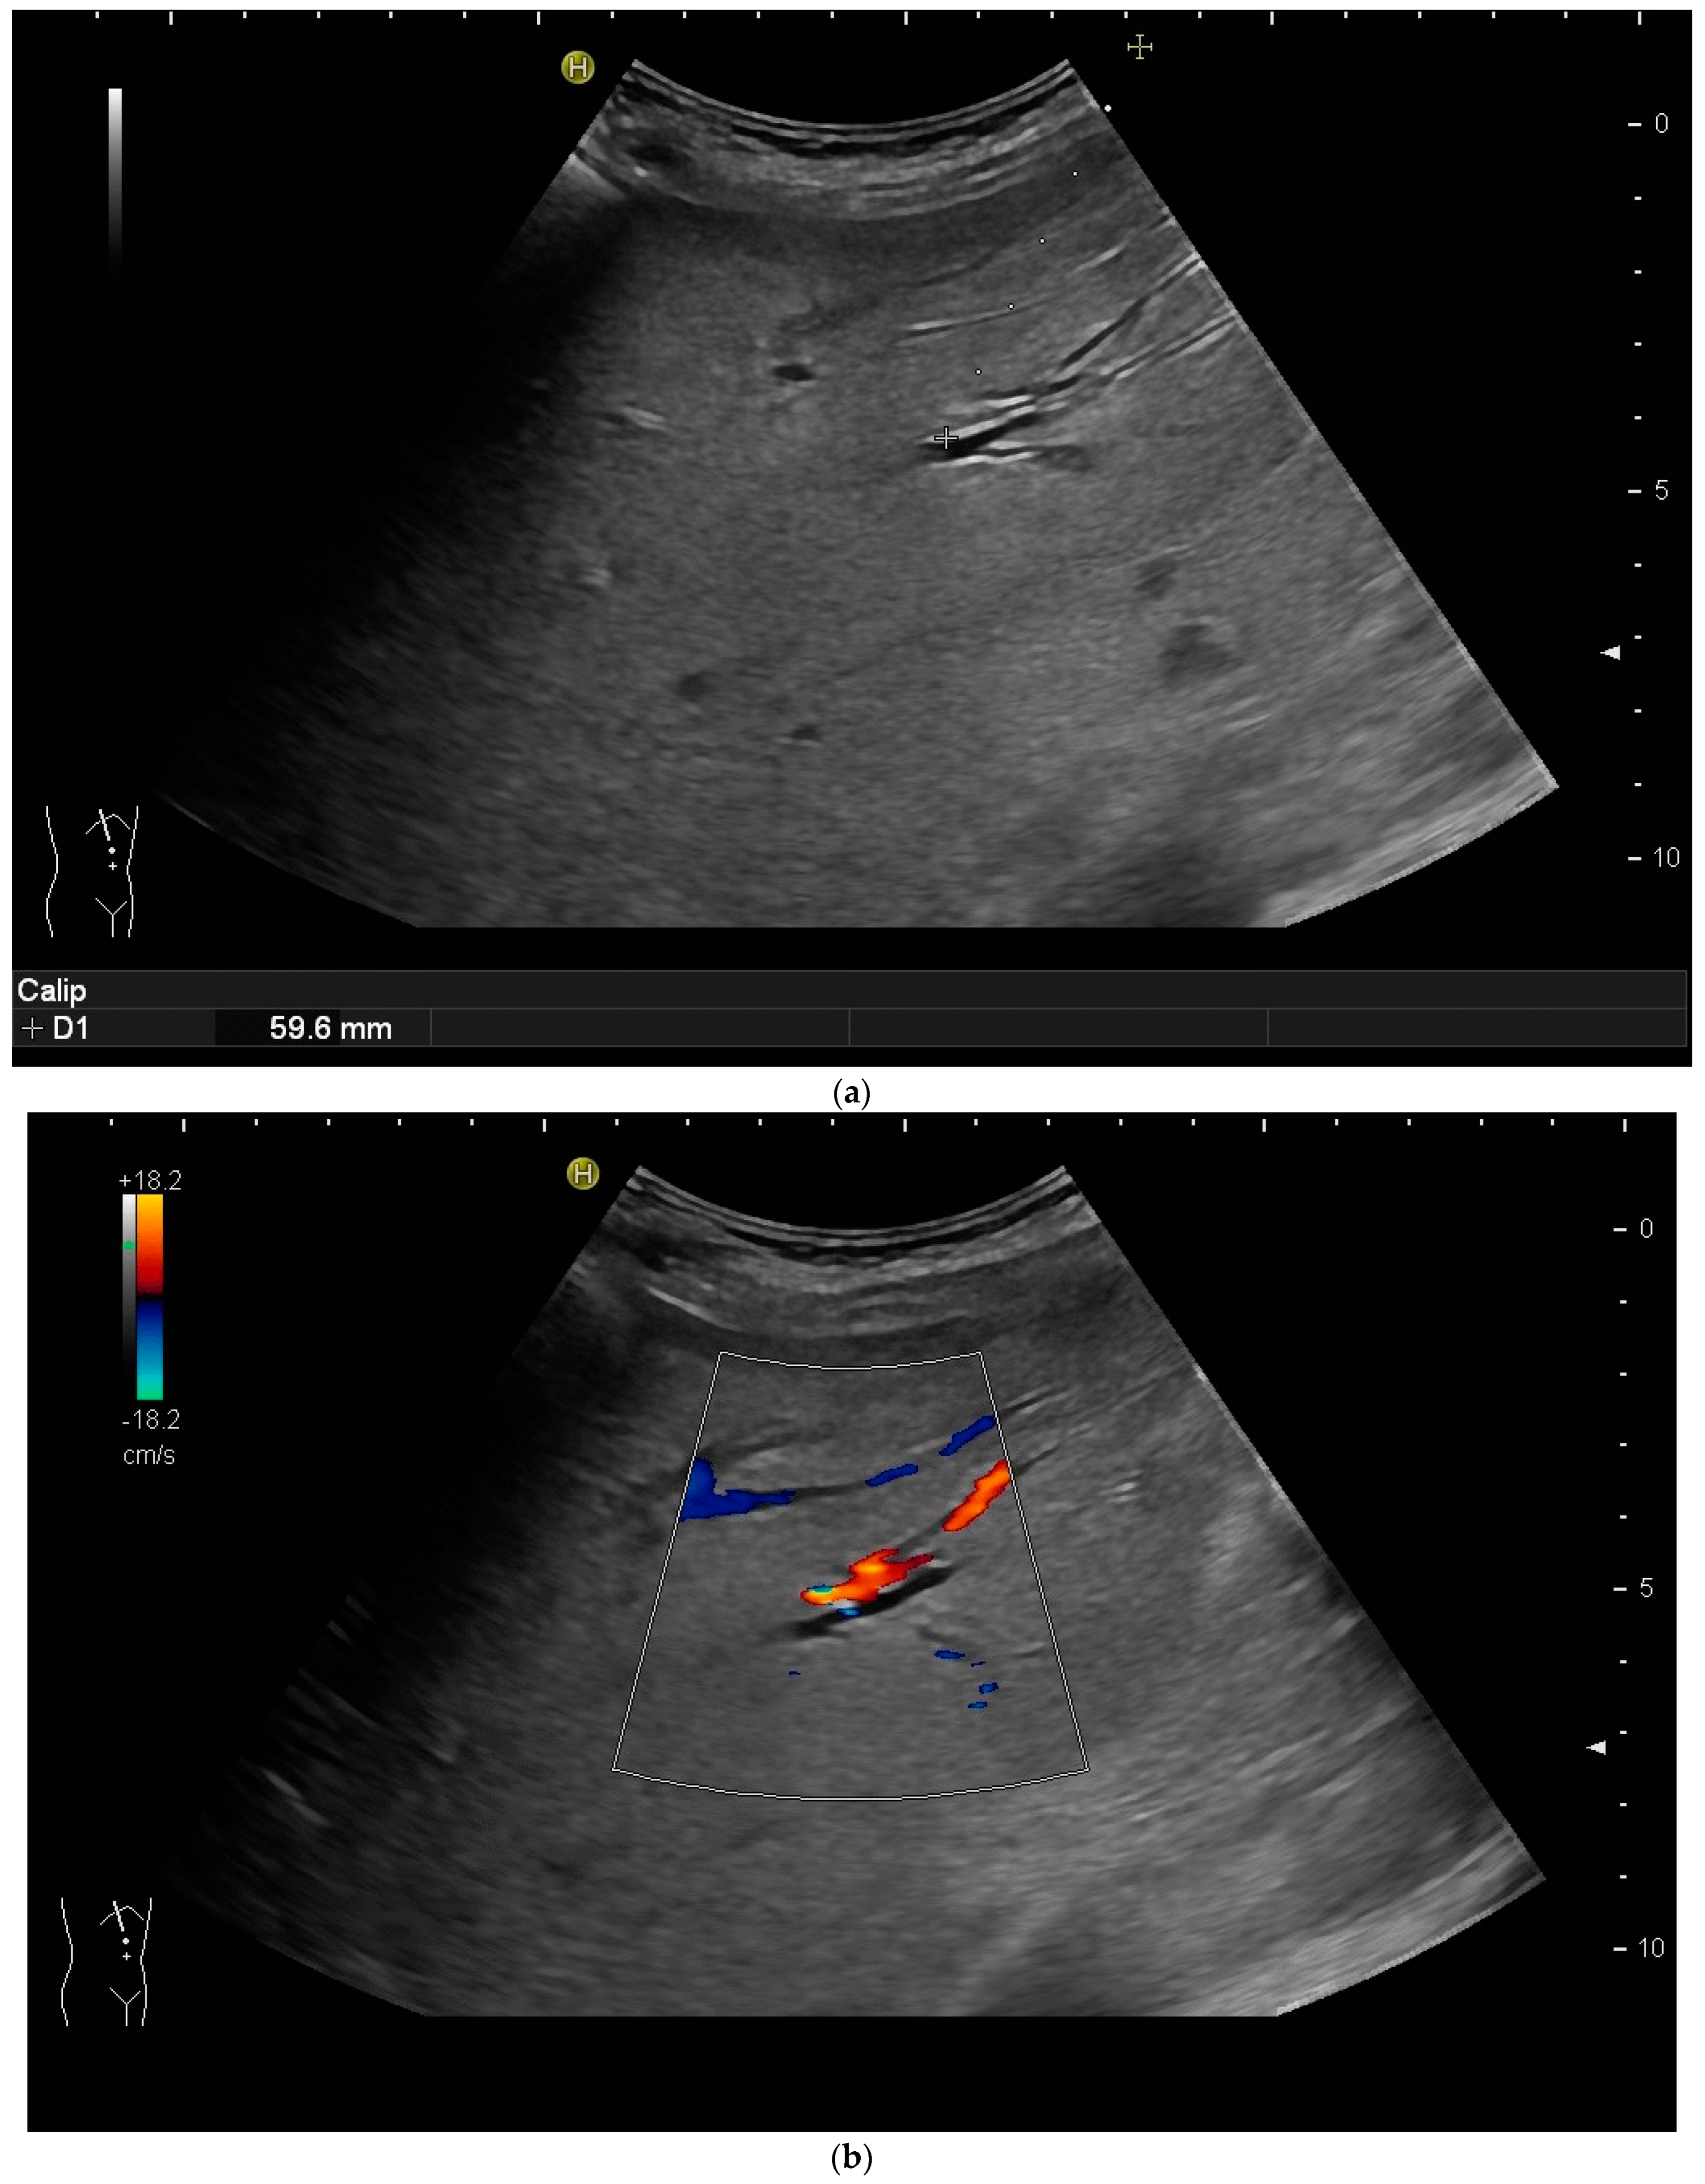

However, the “free hand” technique allows for every puncture angle and is, therefore, preferred by us. The use of colour Doppler will enable the doctor to avoid blood vessels and identify smaller bile ducts (Figure 3a,b).

Figure 3.

(a) Hypoechoic tubular structures in Segment V are visualised in an intercostal view; (b) Colour Doppler helps to differentiate between bile ducts and blood vessels.

In cases of extrahepatic obstruction, mostly the right liver lobe will be addressed. It is common practice to head for the peripheral branches in Segment V (cf. Figure 3a,b), as from there to the common bile duct, the biliary branches form a harmonic arch, and the forward movement of the guide wire seems unpretentious [3]. However, US guidance allows the puncture of any biliary duct of the right or left liver lobe that can be depicted well (Figure 4a–c).

The biliary system can be punctured in the right or left liver lobe, depending on the level of obstruction or medical needs. In dilated intrahepatic ducts, accessing the bile ducts with a needle and advancing a wire with the subsequent placement of drainage is easier, and adverse events are fewer than in nondilated ducts. It is also possible to access nondilated ducts, but ideally, a duct with a diameter of ≥3 mm should be aimed for. As bile ducts run in parallel to portal veins, nondilated bile ducts can be found by using colour Doppler and heading for a portal vessel visualised thereby—the so-called parallel technique [20,31,37,38,39]. Ideally, the angle between the duct and needle should be less than 90 degrees [40].